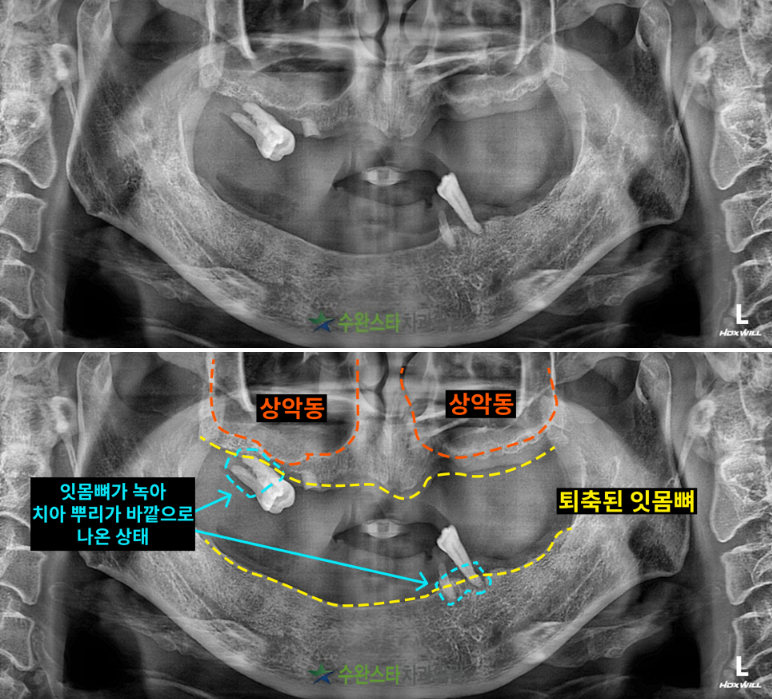

내원 시 파노라마

처음 내원 시 파노라마, 60대 남성 (2025.2 촬영)

내원 시 파노라마 사진입니다.

구강 내부 사진과 마찬가지로

상악과 하악 모두에서 잇몸뼈가

녹아있는 게  관찰되었습니다.

잇몸뼈가 많이 녹은 경우

자연치아를 살릴 수 없어

발치 후 뼈 이식과 임플란트가

필요합니다.

특히 상악은

상악동과 인접한 부위까지

뼈가 많이 퇴축되어 있었고,

하늘색으로 표시한 부분은

치아 뿌리가 노출된

모습을 볼 수 있습니다.

이처럼 잇몸뼈가 부족한 경우에는

상악동 거상술을 통한

전체적으로 뼈이식이 필요합니다.